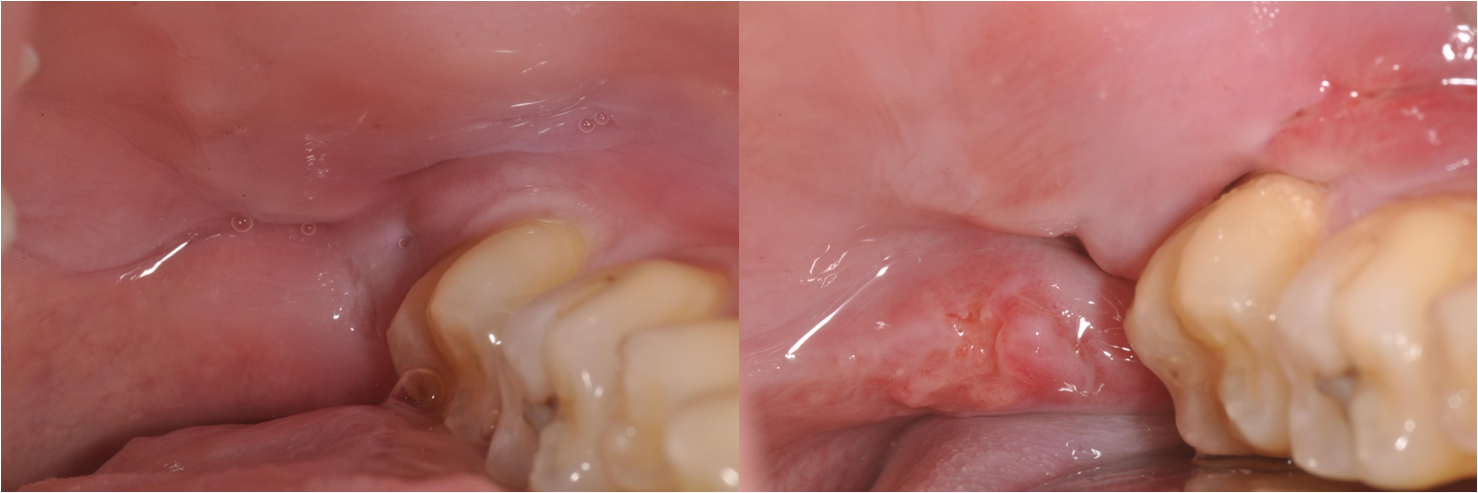

拔牙後傷修處理-卡食物-#38

口腔外科

拔牙後傷口處理